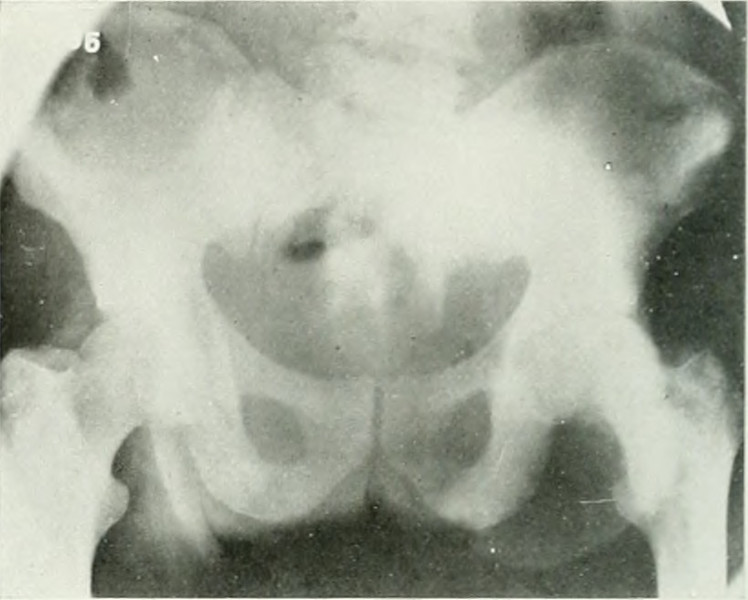

After some time into his recovery from the depleting and debilitating side effects of his radiation therapy, my father began genetic counseling. Or, rather, the part of our nuclear unit defined by patrilineal consanguinity began genetic counseling. My father had his blood tested to look for mutated genetic markers that indicate elevated risk for disease or illness. Daddy had an especially aggressive grade of prostate cancer4, which places my brother at potentially elevated risk for testicular cancer, both of us at increased risk for pancreatic cancer, and me at potentially elevated risk for breast and ovarian cancers.

4. The Gleason score for grades of prostate cancer describes the resemblance between normal cells and cancerous cells. Grade 1 cells resemble normal prostate tissue, whereas grade 5 cells are so cancerous and mutated that they no longer look like normal cells. The Gleason score ranges in theory from 2 to 10, but 6 to 10 in practice; 6 or lower is low grade, 7 is intermediate, and 8–10 is high. My father’s score was a 9.